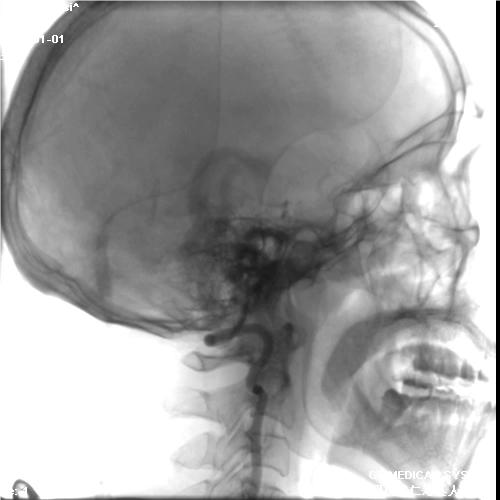

初始造影RICA起始位

病历夹什么径技·第152期|串联营病历夹:川陕大营_https://www.jmylbn.com_新闻资讯_第81张

初始造影后循环+LICA正位

病历夹什么径技·第152期|串联营病历夹:川陕大营_https://www.jmylbn.com_新闻资讯_第82张